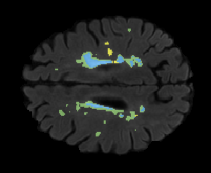

Table 2: Segmentation results for all proposed methods, each column represent a different slide in the image, blue areas are regions which were correctly labeled, false positives are shown in green, and false negatives in yellow

In order to better understand the above results, we visually analyzed the output segmentation performed for each method. Table 2 shows the results for three different slices (one slice per column). As illustrated, the proposed method is able to produce less false positives. It is also important to note that, unimodal segmentation is the one that produces more false positives, showing the advantage of using synthetic data. Regarding the nature of false positives, it can be easy to see in the third column a large number of false positives are on the border of periventricular lesions for the Unimodal method in comparison to the proposed method. Also from the first and second column, it can be observed that Unimodal tend to produce more small regions of false positives near to cortical areas. Removing such false positives requires additional post-processing steps, therefore, it is of value avoid this kind of over-segmentation. It can also be noted that synthesis methods tend to produce the same kind of false negatives, this may be due to the blurring effects in synthesized images since the information available during testing is limited – which otherwise is available from a FLAIR sequence.